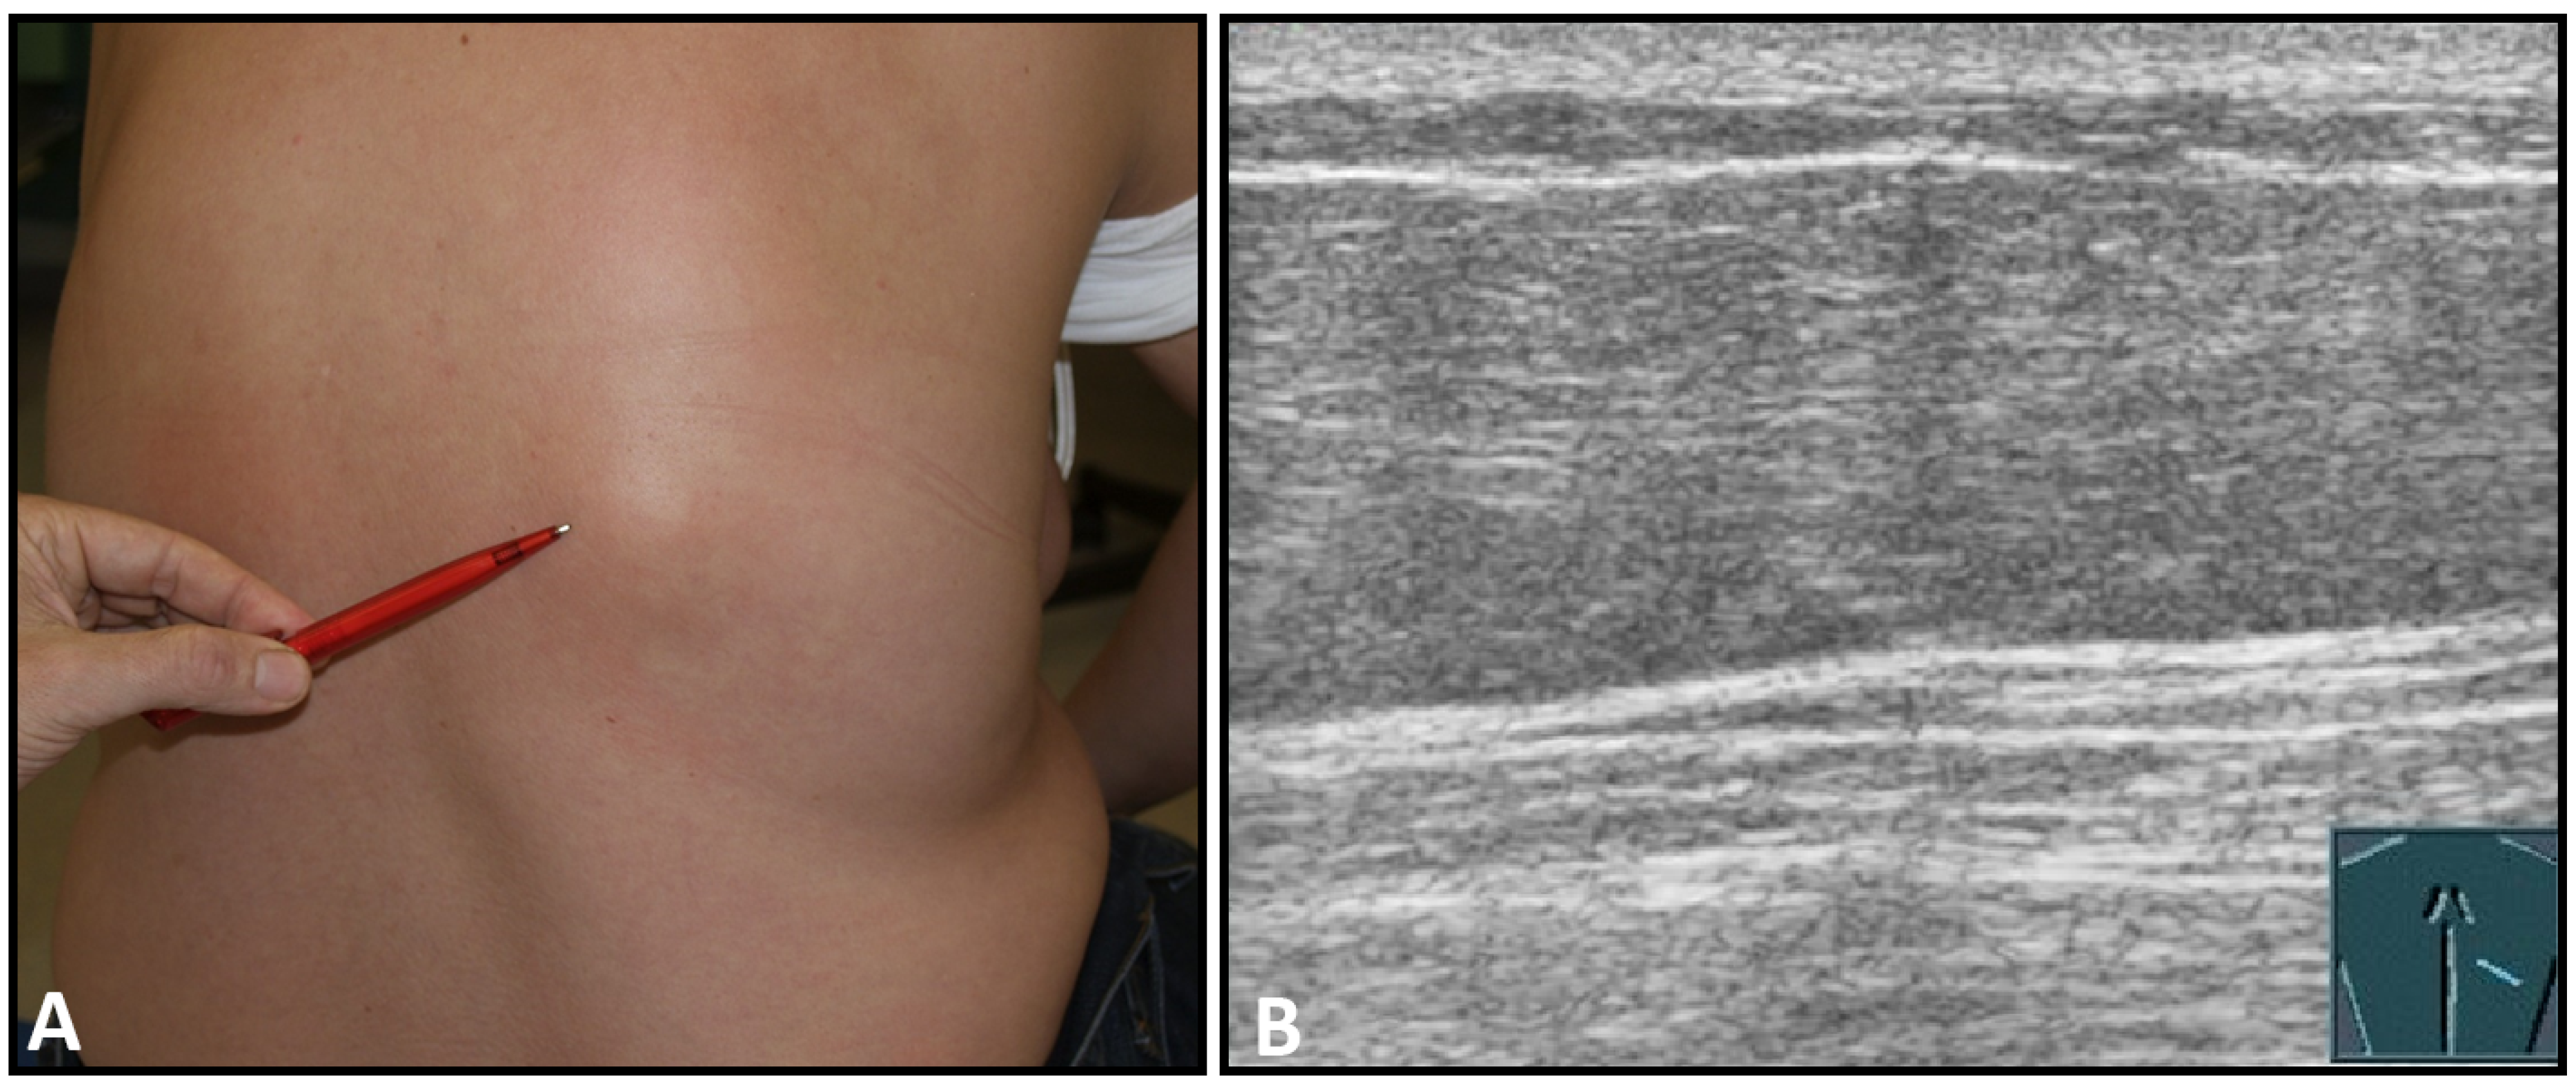

Fractures of ribs or the sternum can be diagnosed by visualizing an interruption of the cortical bone contour. Frequently, a step formation with a surrounding hematoma is found, which is visualized as a blurred-bounded, inhomogeneous, hypoechoic structure (Figure 4). Imaging of reparative processes and contusions is possible. In principle, traumatic fractures cannot be differentiated from pathological fractures unless a tumor soft tissue mantle can be visualized.

Figure 4.

Illustration of different patterns of traumatic rib fractures: (A) major step formation with hematoma (arrow); (B) minor step formation; (C) minimal contour disruption (arrow) with small hematoma; (D) small impression (arrow) with hematoma; and (E) long-standing fractures with bone consolidation.